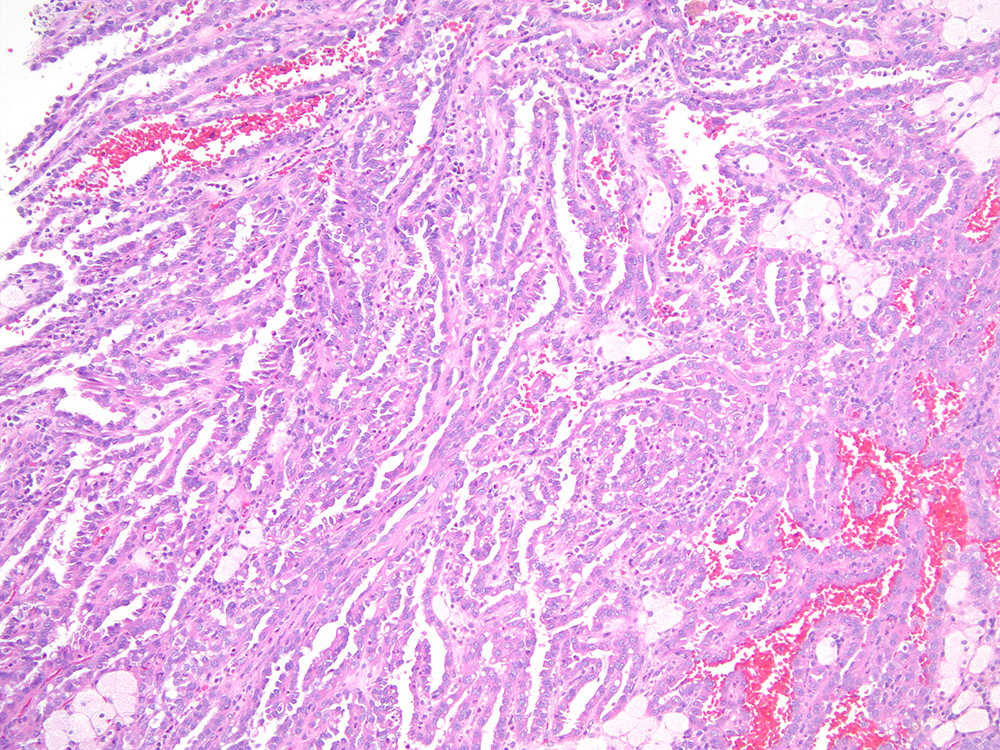

Renal tumor grading

Case ID: 713